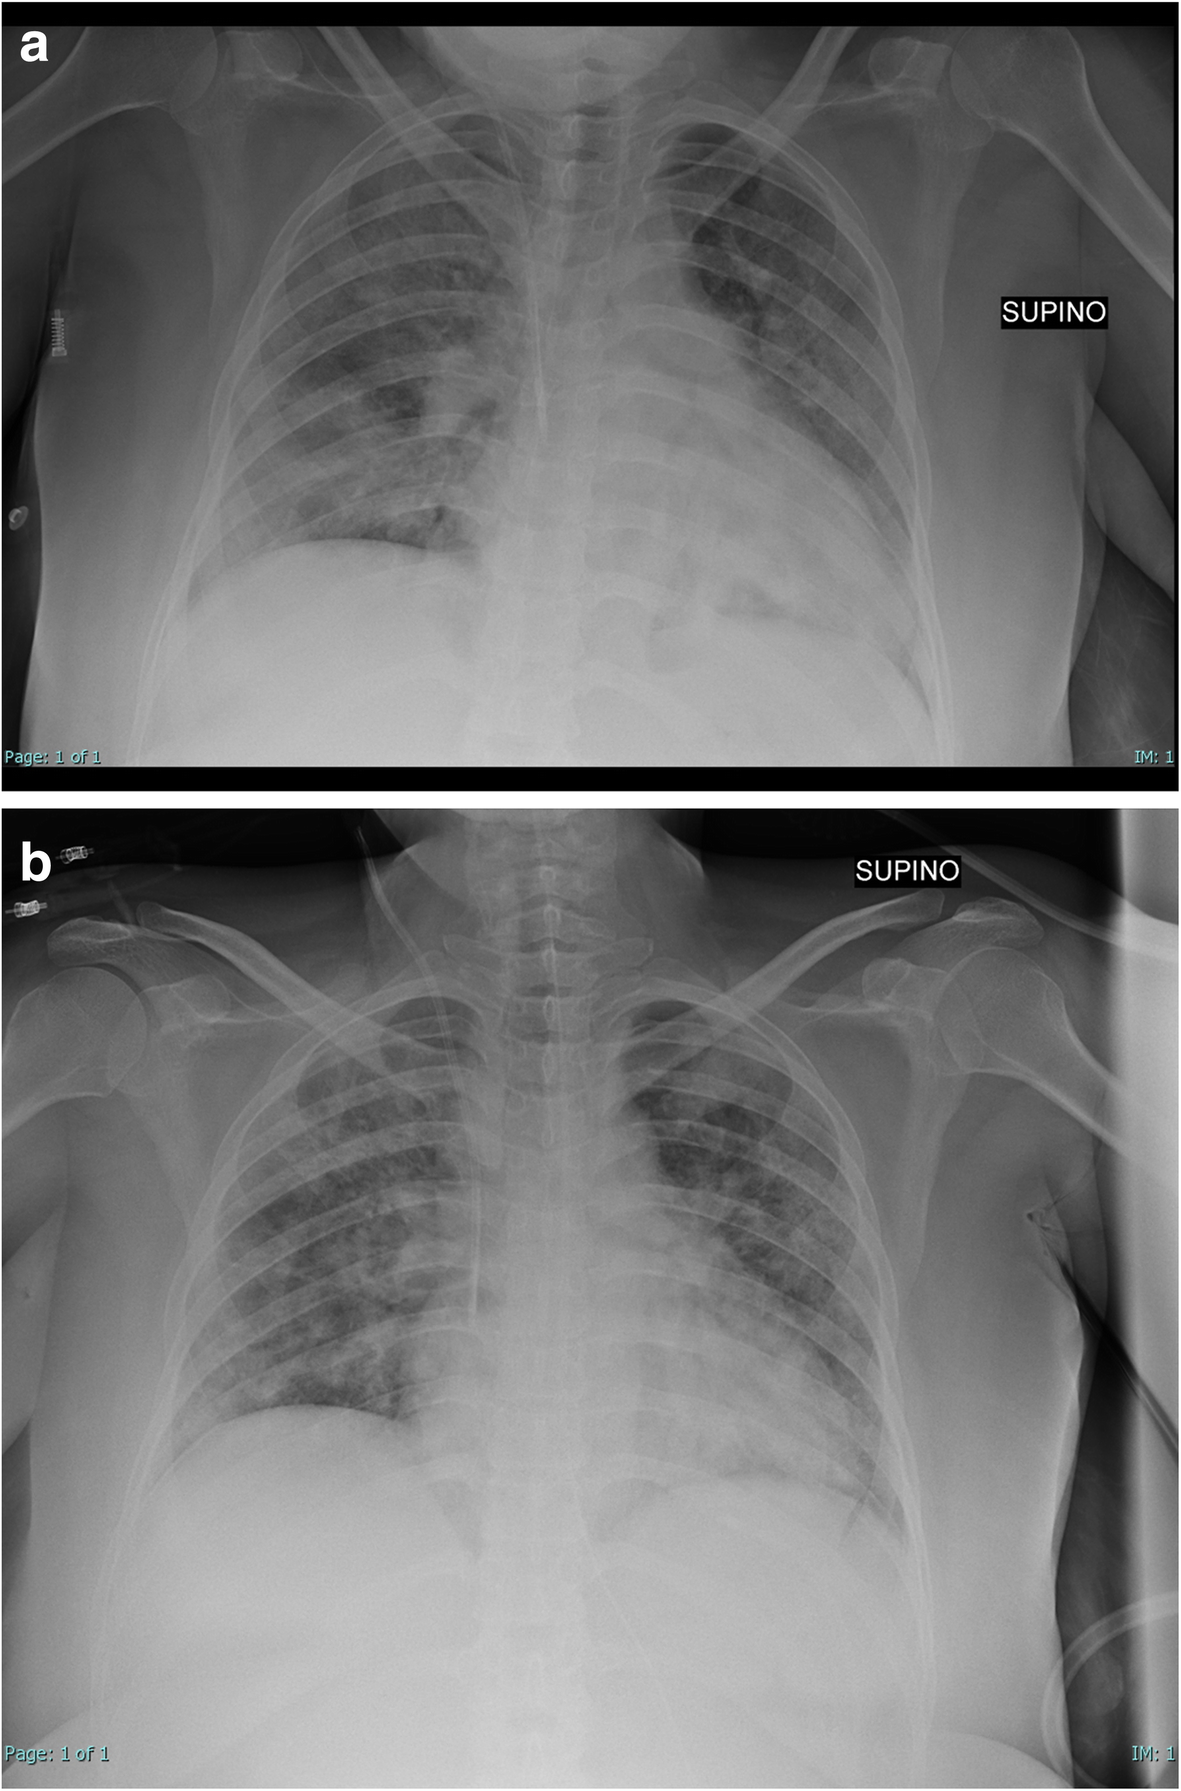

Here we report a case of a 40-year-old Moroccan woman, at the 22th week of gestational age, with only hypothyroidism in anamnesis. She was admitted to our Emergency department for COVID-19 bilateral pneumonia, after 10 days from the beginning of symptoms (fever and cough), and after 2 days of hospitalization in the medical department, where respiratory dynamic and exchanges worsened, although incremental FiO2). At ICU admission (day 0, D0) she had tachypnea and severe hypoxia (PaO2/FiO2 of 60 in high flow nasal cannula (HFNC)). She was initially treated with steroids (dexamethasone 6 mg daily for 7 days), prophylactic Low Molecular Weight Heparin and non-invasive ventilation with full-face mask, reaching a PaO2/FiO2 of 116. Lung ultrasounds were provided daily to the patient [4], documenting multiple subpleural anterior, posterior and inferior lung consolidations, without pneumothorax or pleural effusion occurence. Her first chest radiography is reported in Fig. 1A. But on D2, for clinical worsening and an increasing severe dyspnea and after a collegial discussion involving also our gynecological department, she was intubated and pronated, undergoing a first long-prone position cycle (72 h, according to our hospital protocol), limiting abdominal and pelvic compression with proper positioning and cushions. The patient was firstly treated with prophylactic dosage of ceftriaxone (5 days), then with vancomycin for increase in inflammation indices and an isolation of a Staphylococcus Aureus in a Braoncoaspiratus. Best PEEP was determined every 12 h, determining it according to our protocols [5]. During the first cycle of the prone position she initially required high Positive End-Expiratory Pressure (PEEP of 14 cmH2O, after 36 h reduced to 12 cmH2O), with a driving pressure of 12 cmH2O, after 48 h (D4) reduced to 10 cmH2O, and a respiratory rate of 16, on D4 reduced to 14, reaching a PaO2/FiO2 of 234 when she was supinated (after 72 h, on D5); However during the first 24 h of supination (still curarized, on D6) her respiratory parameters worsened, so she underwent a second cycle of prolonged prone position, requiring similar ventilation settings. After another 72 h, she reached a P/F of 290, so she was finally supinated at D9. PaCO2 was always maintained at a range 35–45 cmH2O. Daily intra-abdominal pressure (IAP) was also performed, starting from an IAP of 10 cmH2O (in the supine position) and reaching a maximum of 13 during prone position. However, since the best PEEP titration in patients with increased IAP is still debated [6], we titrated it on the sole base of ARDS protocols [5]. No maternal complications due to prolonged prone position were observed, and daily and obstetric monitoring of fetal well-being with cardiotocography and weekly ultrasounds and maternal uterine artery Doppler flow velocimetry were performed; Even if an umbilical arterial systolic/diastolic ratio decrease can be expected in the prone position [7], we did not observe them, maybe because obstetric evaluations were performed in right lateral decubitus when the patient was in the prone position. However, no fetal sufferance signs were shown.

Fig. 1

a Chest radiography of the pregnant woman before intubation, at ICU admission. b Chest radiography of the pregnant woman after extubation (15th day)

She was finally extubated on D15 (Fig. 1B), supported with HFNC until discharge in the medical department (D20), and finally discharged from the hospital on D26. All of the obstetric monitoring showed fetal activity, compatible with the maternal sedation status.